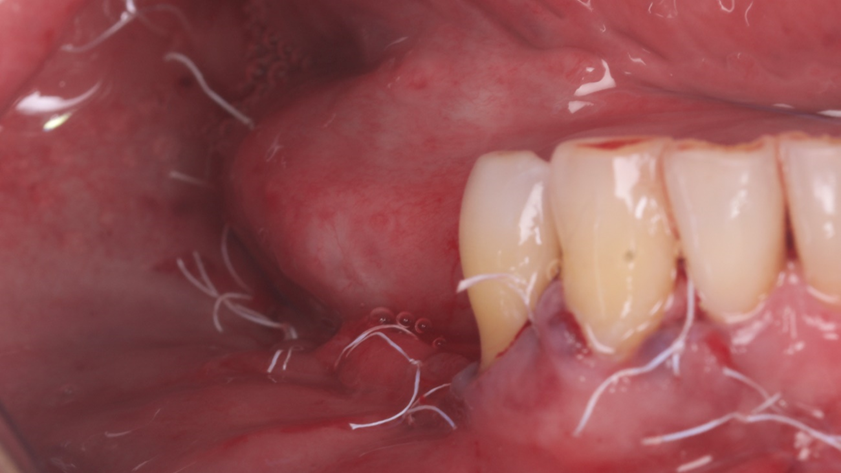

Homem de 60 anos foi encaminhado para reabilitação implantossuportada na região molar inferior direita (Figura 1). O volume ósseo remanescente tridimensional foi acessado por meio de tomografia computadorizada. Revelou uma deficiência vertical de modo que um aumento vertical foi planejado antes da colocação do implante. Seu histórico médico foi verificado e não foram encontradas comorbidades nem condições alérgicas. Não houve achados clínicos intraorais anormais, mas uma deficiência vertical na área molar inferior direita. Nenhum achado anormal foi perceptível no exame extraoral. Um enxerto autógeno em bloco ósseo dividido foi planejado para aumento horizontal e o ramo ipsilateral foi o local doador de escolha. A cirurgia foi realizada sob anestesia local com Articaína 4% e adrenalina 1:100.000. O paciente foi prescrito para enxaguar com Clorexidina 0,12% no pré-operatório, bem como tomar 1mg de Amoxicilina e 8mg de Dexametasona P.O. uma hora antes da cirurgia. Uma incisão mucoperiosteal foi realizada com bisturi número 15C desde o ramo mandibular até a borda mesiovestibular do primeiro pré-molar juntamente com uma incisão perpendicular obliquamente no vestíbulo mandibular. Após o descolamento da mucosa vestibular e liberação do nervo mentoniano, a mucosa lingual também foi descolada (Figura 2). Duas osteotomias verticais e uma horizontal foram realizadas no ramo mandibular com broca 701 para retirada do bloco ósseo necessário à reconstrução horizontal (Figura 3). Após a retirada do enxerto com auxílio de um elevador radicular, o bloco foi cortado longitudinalmente em dois pedaços finos com brocas discais e o osso esponjoso foi raspado para que pudesse ser utilizado como osso lascado (Figuras 4 a 8). Os blocos foram fixados na área edêntula. Um bloco foi fixado na face vestibular e o outro na face lingual. Cada um deles foi fixado com dois parafusos de osteossíntese de 1,5 mm e o osso lascado foi inserido no espaço entre eles (Figuras 9 e 10). A ferida foi fechada com fio de polipropileno 5-0, que foi retirado após 15 dias (Figura 11). A cirurgia cicatrizou sem intercorrências e o paciente recebeu prescrição de amoxicilina 500 mg P.O. a cada oito horas durante sete dias e ibuprofeno 600 mg a cada seis horas durante cinco dias.